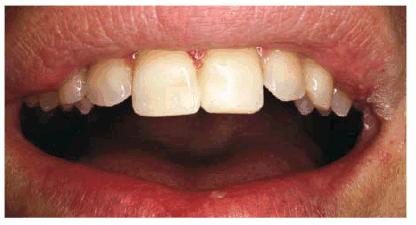

PROBLEM: A 27-year-old male presented with fractured maxillary central

incisors involving the incisal edges (Figur 323s1823d e 18-6A). Because the patient preferred not

to reduce the tooth structure, a bonded composite resin was the material of

choice to restore the fractured edges.

Figur 323s1823d e 18-6A: This 27-year-old man fractured his maxillary central incisors.

TREATMENT: Since the left central incisor overlapped the right one, the

mesial surface of the left central was reshaped slightly to reduce the amount

of overlapping in an attempt to create an illusion of straightness (Figur 323s1823d e 18-6B). These fractures were old and not

sensitive, so no protective base was required. In a new fracture or pulp

exposure, the fracture site would have been protected first with glass ionomer

liner. A large particle composite restoration was used for strength and to help

blend in translucency. The restorations were finished with conventional

composite resin finishing techniques (see Chapter 13, Esthetics in Dentistry,

Volume 1, 2nd Edition).

Figur 323s1823d e 18-6B: After light cosmetic contouring to the left central incisor, both central incisors were bonded with a large particle composite resin.